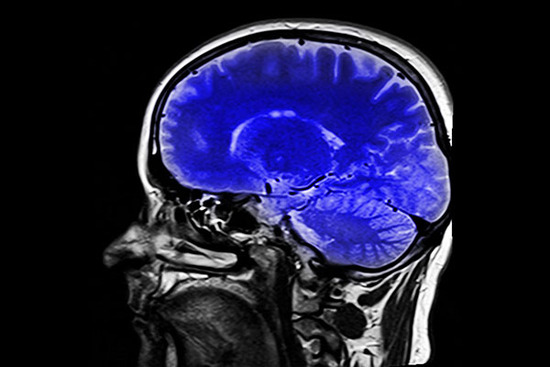

新研究表明,我们功能性磁共振成像技术(fMRI)的算法可能不对——研究人员在fMRI专用软件中发现一个算法错误,这个错误可能导致过去15年中关于人类大脑活动的研究变成一纸空文。

目前,研究大脑活动的最佳方式是功能性磁共振成像技术(fMRI)。fMRI是如此好用,以至于我们对其相当依赖——当然,只要fMRI准确又可靠,这也不是什么坏事。

fMRI用于观察人们运动、游戏、恋爱以及用药时大脑的变化,一旦其出现问题,多年来的科研成果都会受到质疑。为了测试fMRI的功能,来自瑞典林雪平大学的研究人员进行了一场规模史无前例的试验,然而试验结果并不乐观。

那么,这一研究方法到底有什么错误呢?fMRI的工作基于一个巨大的磁场,磁场在穿过人体时会捕捉到大脑局部血流的变化,这些微小的变化代表大脑特定区域活动的增加或减少,软件也是根据这一原理进行解析的。但问题在于,观察数据时,科学家看到的不是真正的大脑——他们看到的大脑的图像由无数的“立体像素”组成,之后通过软件编译出来,理查德·查温这样对登记簿网说道。